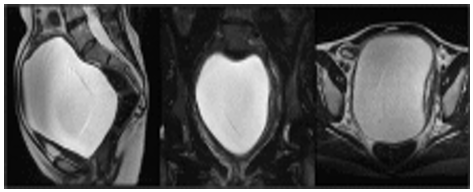

A 43-year-old nulliparous woman presented with complaints of a lower abdominal palpable mass of 1-year evolution and voiding difficulties for 6 months. A pelvic magnetic resonance imaging (MRI) (Figure 1) revealed a paracervical cyst measuring 15.4 x 13.5 cm in the right paracervical region.

(A) Sagittal T2-weighted image demonstrated an enormous Gartner duct cyst, up to 15.4 cm in its greatest diameter in the paracervical and paravaginal region.

(B) An enhanced homogeneous cyst enclosed in a capsule on a coronal T2-weighted image.

(C) The cyst distorted the cervix onto the left side 80.

Figure 1: A magnetic resonance scan of the pelvis before the second operation.